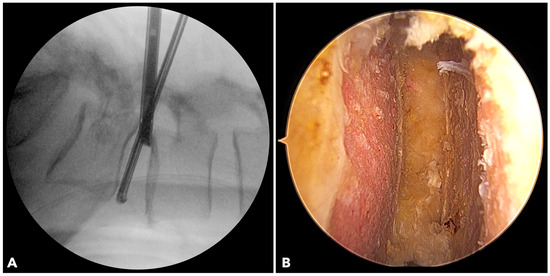

Improved Clinical and Radiological Outcomes with Double-Cage Biportal Endoscopic Transforaminal Lumbar Interbody Fusion: A Comparative CT-Based Study

by Yu-Hao Huang and Jwo-Luen Pao

Diagnostics 2025, 15(20), 2652; https://doi.org/10.3390/diagnostics15202652 - 21 Oct 2025

Cited by 1 | Viewed by 1504

Abstract

Background/Objectives: When transitioning from an older surgical technique to a newer one, we expect improved treatment outcomes and fewer complications. However, direct comparative studies to confirm these advantages are often lacking. Tubular minimally invasive transforaminal lumbar interbody fusion (MISTLIF) has been widely [...] Read more.

Background/Objectives: When transitioning from an older surgical technique to a newer one, we expect improved treatment outcomes and fewer complications. However, direct comparative studies to confirm these advantages are often lacking. Tubular minimally invasive transforaminal lumbar interbody fusion (MISTLIF) has been widely used, but limitations in visualization and endplate preparation may compromise fusion quality. Biportal endoscopic TLIF (BETLIF), a more recent alternative, offers enhanced magnification and superior hemostasis. Still, CT-based comparative data on fusion integrity remain limited. To evaluate the clinical and radiological outcomes following a chronological transition from MISTLIF to BETLIF, using thin-slice CT to assess fusion integrity. Methods: This retrospective study analyzed 179 patients treated by a single surgeon between January 2018 and May 2021. The first 90 cases underwent MISTLIF, followed by 89 BETLIF procedures. Clinical outcomes included Visual Analog Scale (VAS), Oswestry Disability Index (ODI), and Japanese Orthopedic Association (JOA) scores. Radiological assessments at one year postoperatively (X-ray and thin-slice CT) included disc height, segmental lordosis, Bridwell fusion grade, cage subsidence, and subchondral osteolysis. Results: BETLIF was associated with significantly shorter hospital stays (5.7 vs. 7.4 days) and fewer transfusions (0% vs. 14.7%). BETLIF showed significantly better ODI (12.7 vs. 23.5), JOA scores (26.4 vs. 20.6), and comparable VAS improvement. Radiologically, BETLIF had significantly higher fusion rates (93.3% vs. 82.4%), greater disc height restoration, and lower rates of cage subsidence (5.0% vs. 13.7%) and osteolysis (13.3% vs. 52.9%). Conclusions: BETLIF demonstrated superior clinical and radiological outcomes, likely due to enhanced endoscopic visualization and precise endplate preparation. Full article

(This article belongs to the Special Issue Diagnosis and Management of Spinal Diseases)

Show Figures

Figure 1